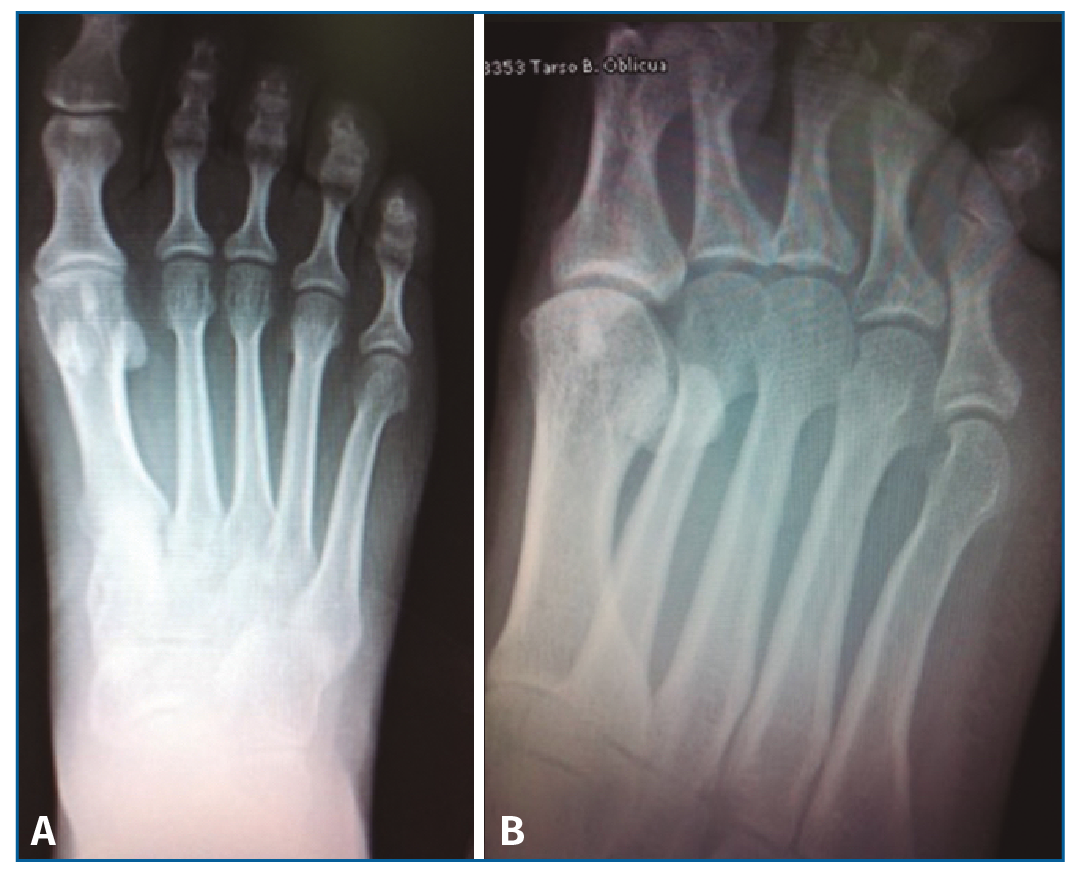

El estudio radiográfico en carga no mostraba alteraciones en la fórmula metatarsal ni lesiones óseas (Figura 1).

Figura 1. Radiología simple anteroposterior en carga (A) y oblicua antepié (B) sin lesiones óseas a nivel del 4.º metatarsiano.